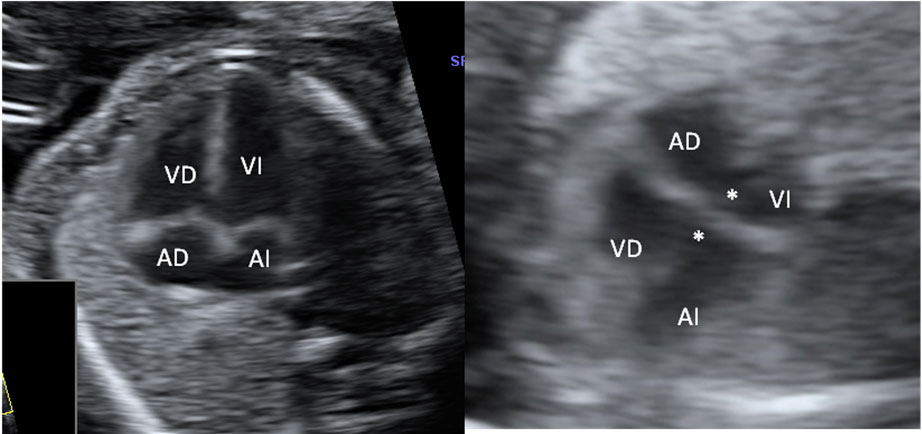

Ecografía Embarazo 2D y 3D Semana 20 - MALFORMACIONES FETALES